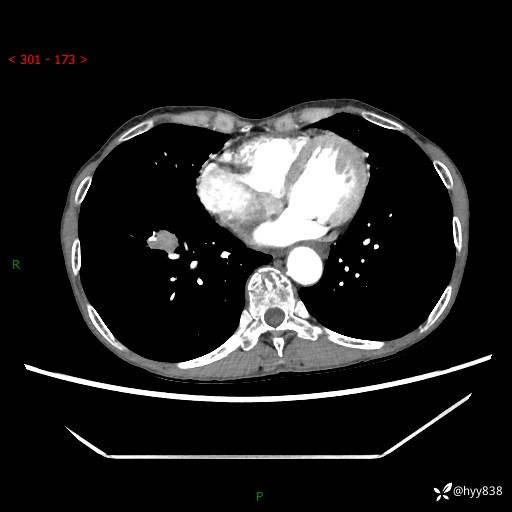

【患者信息】:69岁/女

【主诉】:发现肺占位3天余

【现病史及既往史】:患者3天余前因既往肺气肿复查胸部CT发现“右肺下叶结节、双肺多发结节、双肺门及纵膈淋巴结增大”,平素偶有咳白色粘液痰,下肢乏力,无明显低热、盗汗、咯血、胸痛、喘气等不适,今为求明显结节性质遂来我院门诊就诊,门诊以“孤立性肺结节”收治入院。 起病以来,患者精神饮食睡眠一般,大小便正常,体力无明细变化,体重近年来较前下降。

【检查】:胸部CT增强